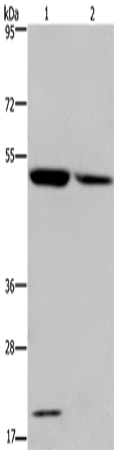

分类: 科研抗体货号: P08198别名: CTX; CP27; CYP27应用: WB,IHC反应种属: Human, Mouse